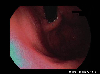

A case of esophageal achalasia which was successfully treated by the Balloon dilatation method.

Endoscopy

abnormal findings of organs/esophageal achalasia